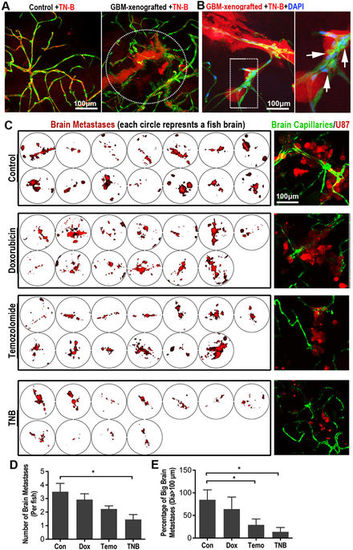

TN-B inhibits the invasion and growth of GBM xenografts in zebrafish brain. (A) TN-B was directly injected into the circulation of 5dpi zebrafish with or without GBM xenografts. Confocal images were taken 1?hour post tracer and drug injection. Dotted circle indicating the tumor area. (B) TN-B and DAPI was injected into the circulation of zebrafish (with 5dpi red GBM xenograft). Confocal images at 8?hours post injection showed the DAPI was still hold in cerebral capillaries (Arrows), indicating the BBB was not destroyed by the TN-B treatment. Area in dotted box was magnified right. (C) Drugs (Doxorubicin, Temozolomide, TN-B and control DMSO) were directly added into the culture medium of living zebrafish embryos (4dpf), which were implanted with GBM-U87 at 3dpf as previously described (n?=?20 in each group). After 3days treatment, all the brains of zebrafish embryos were imaged with confocal microscope. Left panels show the intracranial GBM metastases (red) in each zebrafish brain. Right panels show representative images of the intracranial GBM cells (red) and cerebral capillaries (green) with high resolution. (D,E) Quantitative analysis of the number of whole GBM metastases or relative big GBM metastases in zebrafish brain with or without drug treatment at 7dpf, diagrams showing means and SEM. |